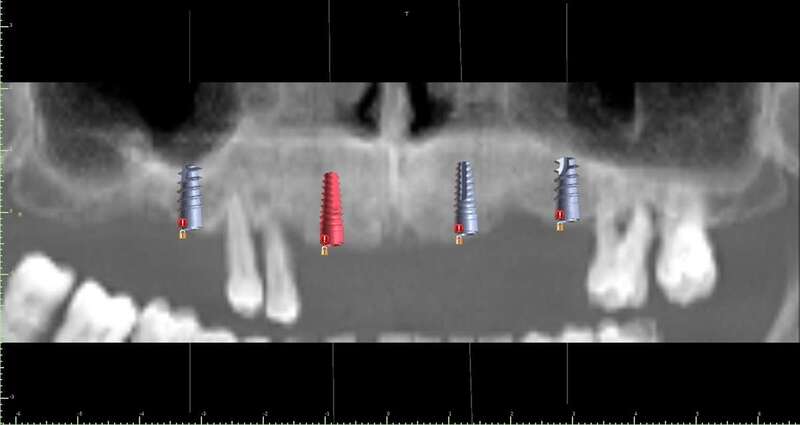

Cirugía guíada por ordenador

El doctor Juan Carlos Rodríguez Pascuas especialista en cirugía de la clínica explica a continuación como funciona y en qué consiste el sistema de cirugía guiado por ordenador:

-Existe un gran abanico de posibilidades para reponer los dientes perdidos con implantes, desde la colocación de unos pocos implantes para reponer todos los dientes, hasta la colocación de implantes y dientes provisionales en el mismo día. Nuestra intención es ofrecer a cada paciente lo que mejor se adapte a su situación. Para ello aprovechamos las últimas tecnologías disponibles, como la Cirugía Guiada por ordenador. Así, el paciente puede ver previamente las opciones que tiene y decidir qué tipo de tratamiento prefiere.

-No. Cada paciente es único y hay varios factores a tener en cuenta. Por ello dedicamos tiempo al estudio y planificación de cada caso para ofrecer el tratamiento ideal para esa persona.

-No tiene por qué serlo. Con los avances tecnológicos que tenemos a disposición, podemos hacer cirugías mínimamente invasivas guiadas por ordenador, que en muchos casos no necesitan ni siquiera puntos de sutura. Durante el tratamiento el paciente no siente ningún dolor y con la adecuada ayuda farmacológica y unos pocos cuidados, en la gran mayoría de los casos no hay ni molestias ni inflamación después de la cirugía.